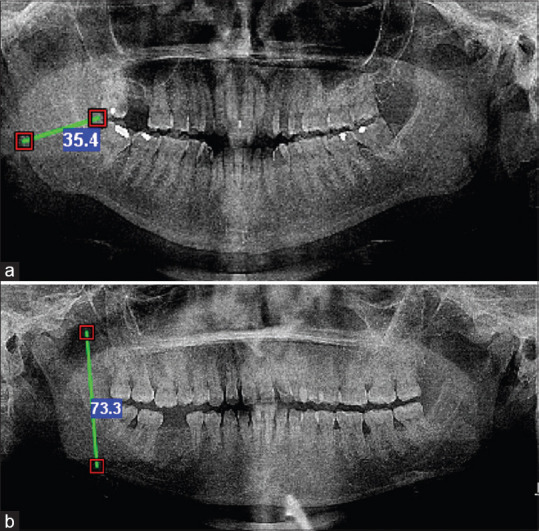

Materials and methods: Sixty orthopantomograms of 30 males and 30 females between the age group of 30 to 40 years were collected. The minimum ramus breath and the coronoid height were measured using a computerized software. The data obtained was statistically analysed using IBM SPSS Statistics for Windows, Version 23.0 (IBM Corp., Armonk, New York, United States) software.

Results: The mean minimal ramus breath and mean coronoid height were greater in males than in females. The mean minimal ramus breath for males was found to be 37.83 ± 2.24 and for females, it was 33.08 ± 4.87 (P = 0.00). The mean coronoid height of males was 80.67 ± 0.83 and that of females was 73.51 ± 1.26 (P = 0.00).